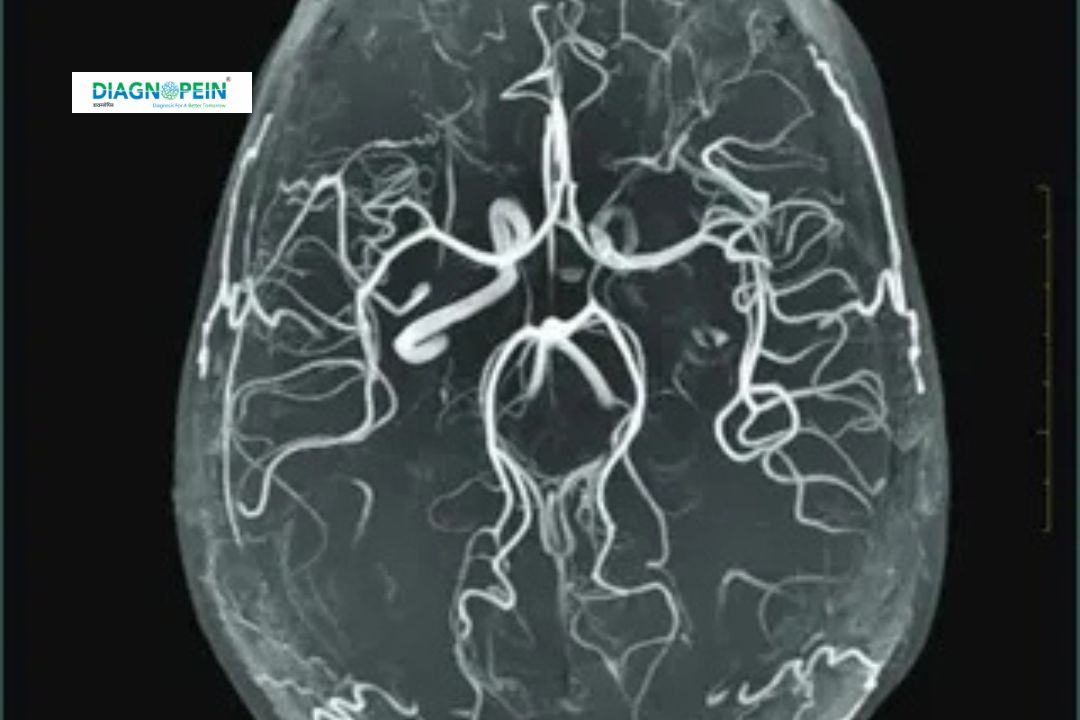

MRI Angiography (MRA) is an advanced imaging technique offered at Diagnopein in Nanded that uses magnetic fields and radio waves to produce detailed images of blood vessels throughout the body. Unlike traditional angiography, MRA does not require catheter insertion or exposure to ionizing radiation, making it a safe and non-invasive procedure. This technology provides high-resolution, 3D views of arteries and veins, helping detect abnormalities in the brain, heart, kidneys, and limbs. It is instrumental in diagnosing vascular diseases such as aneurysms, arterial blockages, stenosis, and malformations, all critical in preventing serious health issues like stroke or heart attacks.